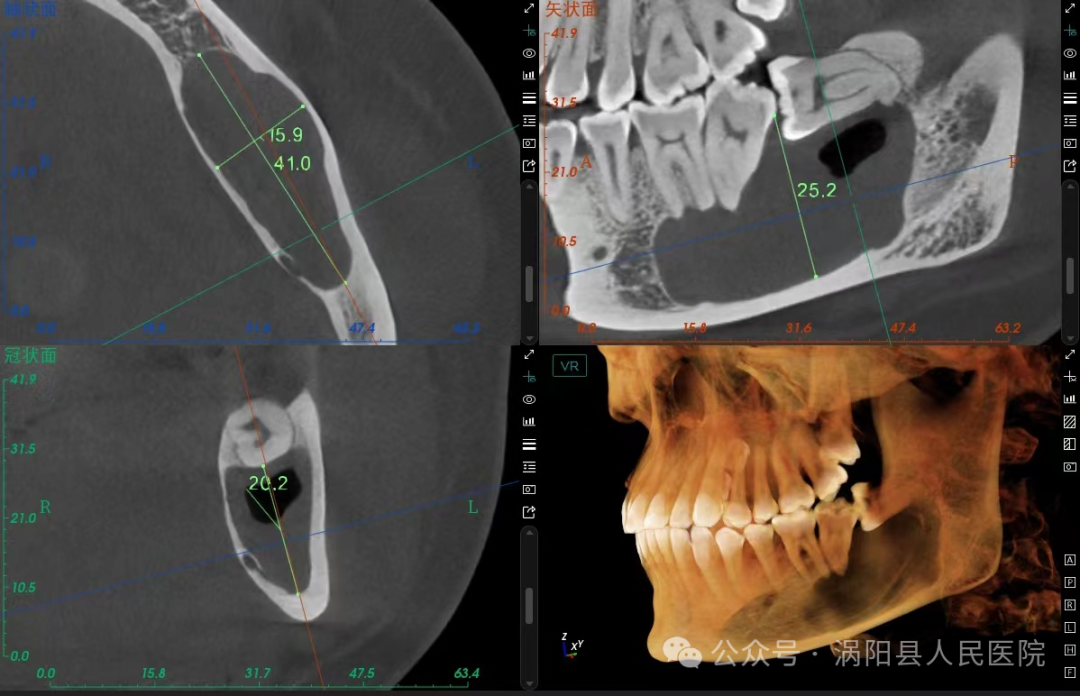

近日,30岁的刘女士因下颌智齿反复发炎至我院就诊,刘女士此前多次想要拔除这颗“惹祸”的智齿,但由于对拔牙过程中锤击等暴力操作的恐惧一直未能下定决心。门诊接诊的杨华一医生通过查看刘女士口内情况和牙片后发现该智齿不仅反复发炎,而且由于长年累月的食物嵌塞,下颌第二磨牙因牙周组织破坏已达到二度松动,如果不及时拔除该阻生智齿,下颌第二磨牙的脱落只是时间问题,甚至还可能引起颌骨囊肿等严重的并发症!

640_看图王.jpg

(使用电刀将牙冠周围的软组织气化,相较于传统的切开翻瓣更快、更精准,出血和术后反应也更轻)